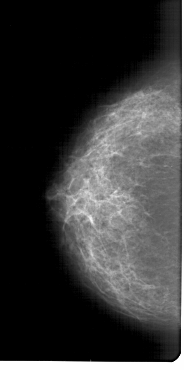

A_1298_1.LEFT_CC

LEFT_CC LINES 6646 PIXELS_PER_LINE 3301 BITS_PER_PIXEL 12 RESOLUTION 43.5 NON_OVERLAY